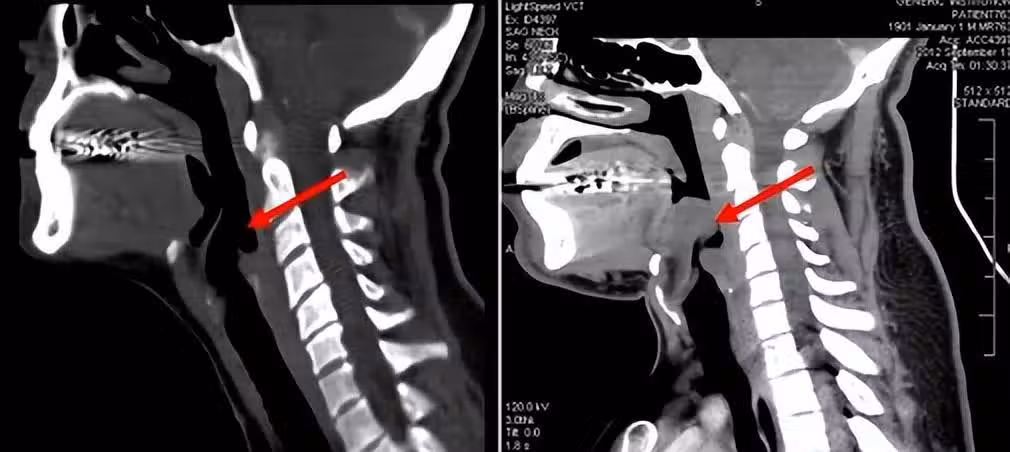

上文中的患者,在聚餐結束後出現咽痛癥狀時,其實那時已經可能因為外部創傷等原因,導致會厭發炎,如果當時及時就醫,或許不會有這麼嚴重的後果。

可她不僅沒有意識到問題的嚴重性,反而擅自服用了消炎藥和海鮮粥,這些很有可能再次引起急性變態反應性會厭炎。

除了死亡率高以外,會厭炎還十分容易誤診,這也是這個病兇險的另一個原因。因為發病時,患者一開始的感受基本都是咽痛、吞咽困難,多數人會以為是扁桃體發炎、咽炎或者感冒,一般不會引起重視。